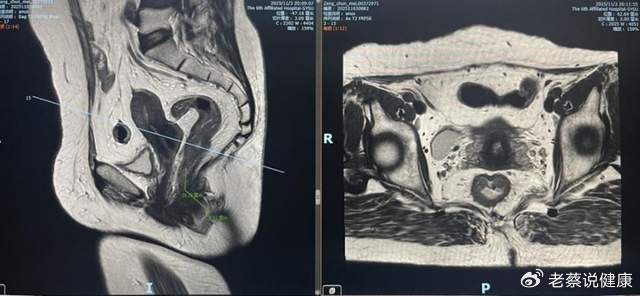

经肛腔镜手术是当前低位直肠肿瘤治疗的热点术式,主要包括经肛微创手术(TAMIS)和经肛全直肠系膜切除术(taTME)两大核心技术。其中,TAMIS 适用于中低位直肠良性肿瘤及早期恶性肿瘤的局部切除,具有创伤小、对肛门括约肌损伤轻微等优势;taTME 则针对肥胖、男性、狭窄骨盆等 “困难骨盆” 患者的低位、超低位直肠肿瘤,可实现超低位保肛,且具有局部复发率低、术后恢复快、手术时间短等特点,能在肿瘤根治的同时显著提升患者术后生活质量。

郑州市中心医院自 2024 年 3 月成功开展首例 taTME 手术以来,已累计完成经肛腔镜相关手术 40 余例,为 40 余名低位直肠肿瘤患者解除病痛的同时,成功保留了患者的肛门功能,实现了 “根治肿瘤 + 功能保护” 的双重目标。凭借在该领域的技术积累与临床优势,医院于 2025 年 3 月正式获批 “郑州市低位直肠癌诊疗中心”,成为郑州市低位直肠癌诊疗的核心示范单位。